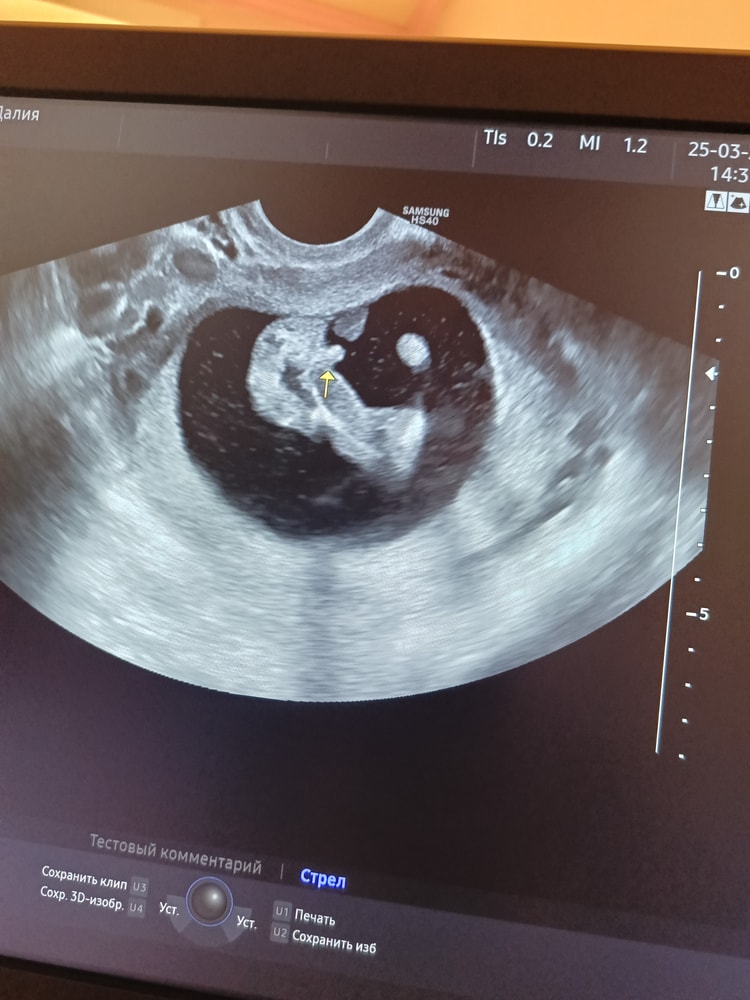

Пол малышаВсем здравствуйте! Хотела бы спросить это мальчик или пуповина? Делала УЗИ платно в 15 недель, врач сказала мальчик 98% , фото УЗИ только половина может поэтому я сомневаюсь, что это половой орган, я конечно очень рада что если это мальчик так как две девочки уже есть.

Я смотрю и мне кажется будто это писюн самый настоящий 😃 не знаю как должна выглядеть пуповина на узи, но когда нам в 16 недель предположили девочку, то там и близко ничего похожего не было на то, что есть на вашем снимке 😁